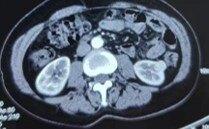

雙腎占位

秦彩朋醫(yī)生的科普號2021年12月23日912